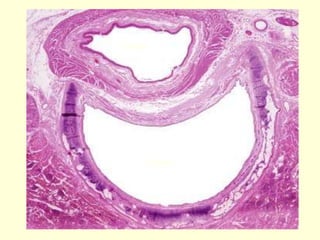

Tráquea

 La tráquea, un tubo corto y flexible (mide unos 2,5

cm de diámetro y más o menos 10 cm de longitud)

que permite el paso del aire y cuya pared

contribuye al acondicionamiento del aire inspirado,

se extiende desde la faringe hasta la mitad del

tórax, su extremo inferior se denomina carina y es

donde se divide en dos bronquios principales.

 La luz de la tráquea se mantiene abierta a causa

de la disposición de sus anillos cartilaginosos

incompletos.

 La pared traqueal está compuesta por:

• Mucosa, compuesta por un epitelio

pseudoestratificado cilíndrico ciliado con células

caliciformes (epitelio respiratorio) y una lámina

propia con fibras elásticas abundantes.

• Submucosa, compuesta por un tejido conectivo

apenas más denso que el de la lámina propia.

• Capa cartilaginosa, compuesta por cartílagos

hialinos con forma de C.

• Adventicia, compuesta por un tejido conectivo

que adhiere la tráquea a las estructuras contiguas.

Bronquios

 La tráquea se divide en dos ramas que forman

los bronquios principales (primarios).

 Al introducirse en el hilio pulmonar cada

bronquio principal se divide en los bronquios

lobares (bronquios secundarios).

 El pulmón izquierdo está dividido en dos

lóbulos, mientras que el derecho lo está en tres.

 Mucosa, que está compuesta por un epitelio

seudo-estratificado cilíndrico con las mismas

células que tiene el epitelio traqueal. La lámina

propia es semejante a la de la tráquea pero su

cantidad disminuye en proporción al diámetro de

los bronquios.

 Muscular, que es una capa continua de músculo

liso en los bronquios mayores. En los bronquios

menores está más adelgazada y menos

organizada y puede aparecer discontinua a causa

de su trayecto espiralado.

 Submucosa, que permanece como un tejido conectivo

bastante laxo. En los bronquios hay glándulas que

siguen a las placas cartilaginosas, es decir que

aparecen en los mismos sectores bronquiales en los que

hay cartílago. Las glándulas bronquiales producen

mucina que, junto con la secretada por las células

caliciformes del epitelio de superficie, forma la capa

mucosa sobre la superficie luminal.

 Capa cartilaginosa, que consiste en placas

cartilaginosas discontinuas.

 Adventicia, que es un tejido conectivo de densidad

moderada que se continúa con el conectivo de las

estructuras contiguas.